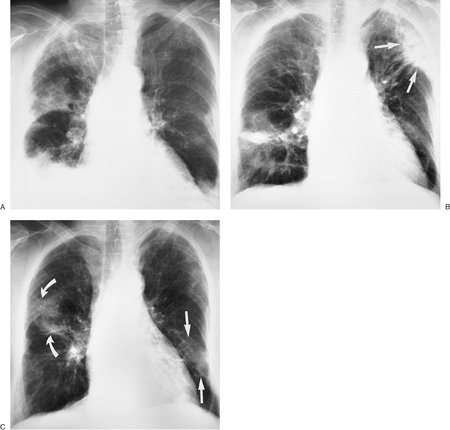

FIGURE 12-5. Chronic eosinophilic pneumonia. A: PA chest radiograph of a 62-year-old woman shows bilateral interstitial and airspace opacities, which are worse in the peripheral lungs, and elevation of the right hemidiaphragm related to right upper lobe volume loss. Based on the findings on this single exam, with no prior chest radiograph for comparison, both acute and chronic processes must be considered. B: CT of the right lung better shows the peripheral distribution of airspace disease. Note air bronchograms (arrows), which are a common feature of EP. No honeycombing is seen. C: PA chest radiograph obtained 2 months later, after treatment with steroids, shows complete clearing of bilateral peripheral lung disease.

Chronic EP is most prevalent in the third to seventh decades of life, with women outnumbering men by 2 to 1 (10). Symptoms of dyspnea, cough, wheeze, malaise, weight loss, fever, and night sweats can be mild or severe. Blood eosinophilia occurs in the majority of patients. Serum IgE is normal or only mildly elevated, which is helpful in distinguishing the condition from allergic bronchopulmonary aspergillosis and tropical and parasitic pulmonary eosinophilias, in which serum IgE levels are markedly elevated. The classic findings on chest radiograph and CT are nonspecific peripheral, nonsegmental, homogeneous alveolar opacities, often with air bronchograms (10,11) (Figs. 12-5 and 12-6). In a minority of patients, the opacities are central in distribution or both central and peripheral (Fig. 12-7). Chronic EP is sensitive to steroid therapy; rapid clearing of radiologic abnormalities is usually seen within a few days, with complete clearing by 1 month. Relapse is common, and the majority of patients need long-term low-dose steroids, distinguishing this disease from acute EP (12). The radiologic manifestations can be migratory, occurring in new locations with relapse.

FIGURE 12-6. Chronic eosinophilic pneumonia, recurrent. A: PA chest radiograph of an 85-year-old woman shows bilateral, ill-defined parenchymal opacities in a predominantly peripheral distribution. The right lung is more involved than the left. B: PA chest radiograph taken 5 months later shows clearing of much of the right lung and worsening disease in the periphery of the left lung (arrows). C: PA chest radiograph obtained 1 month after (B) shows partial clearing of the left upper lung, worsening disease in the left mid peripheral lung (straight arrows), and worsening disease in the right middle lung (curved arrows). Migratory lung disease is a characteristic feature of EP.